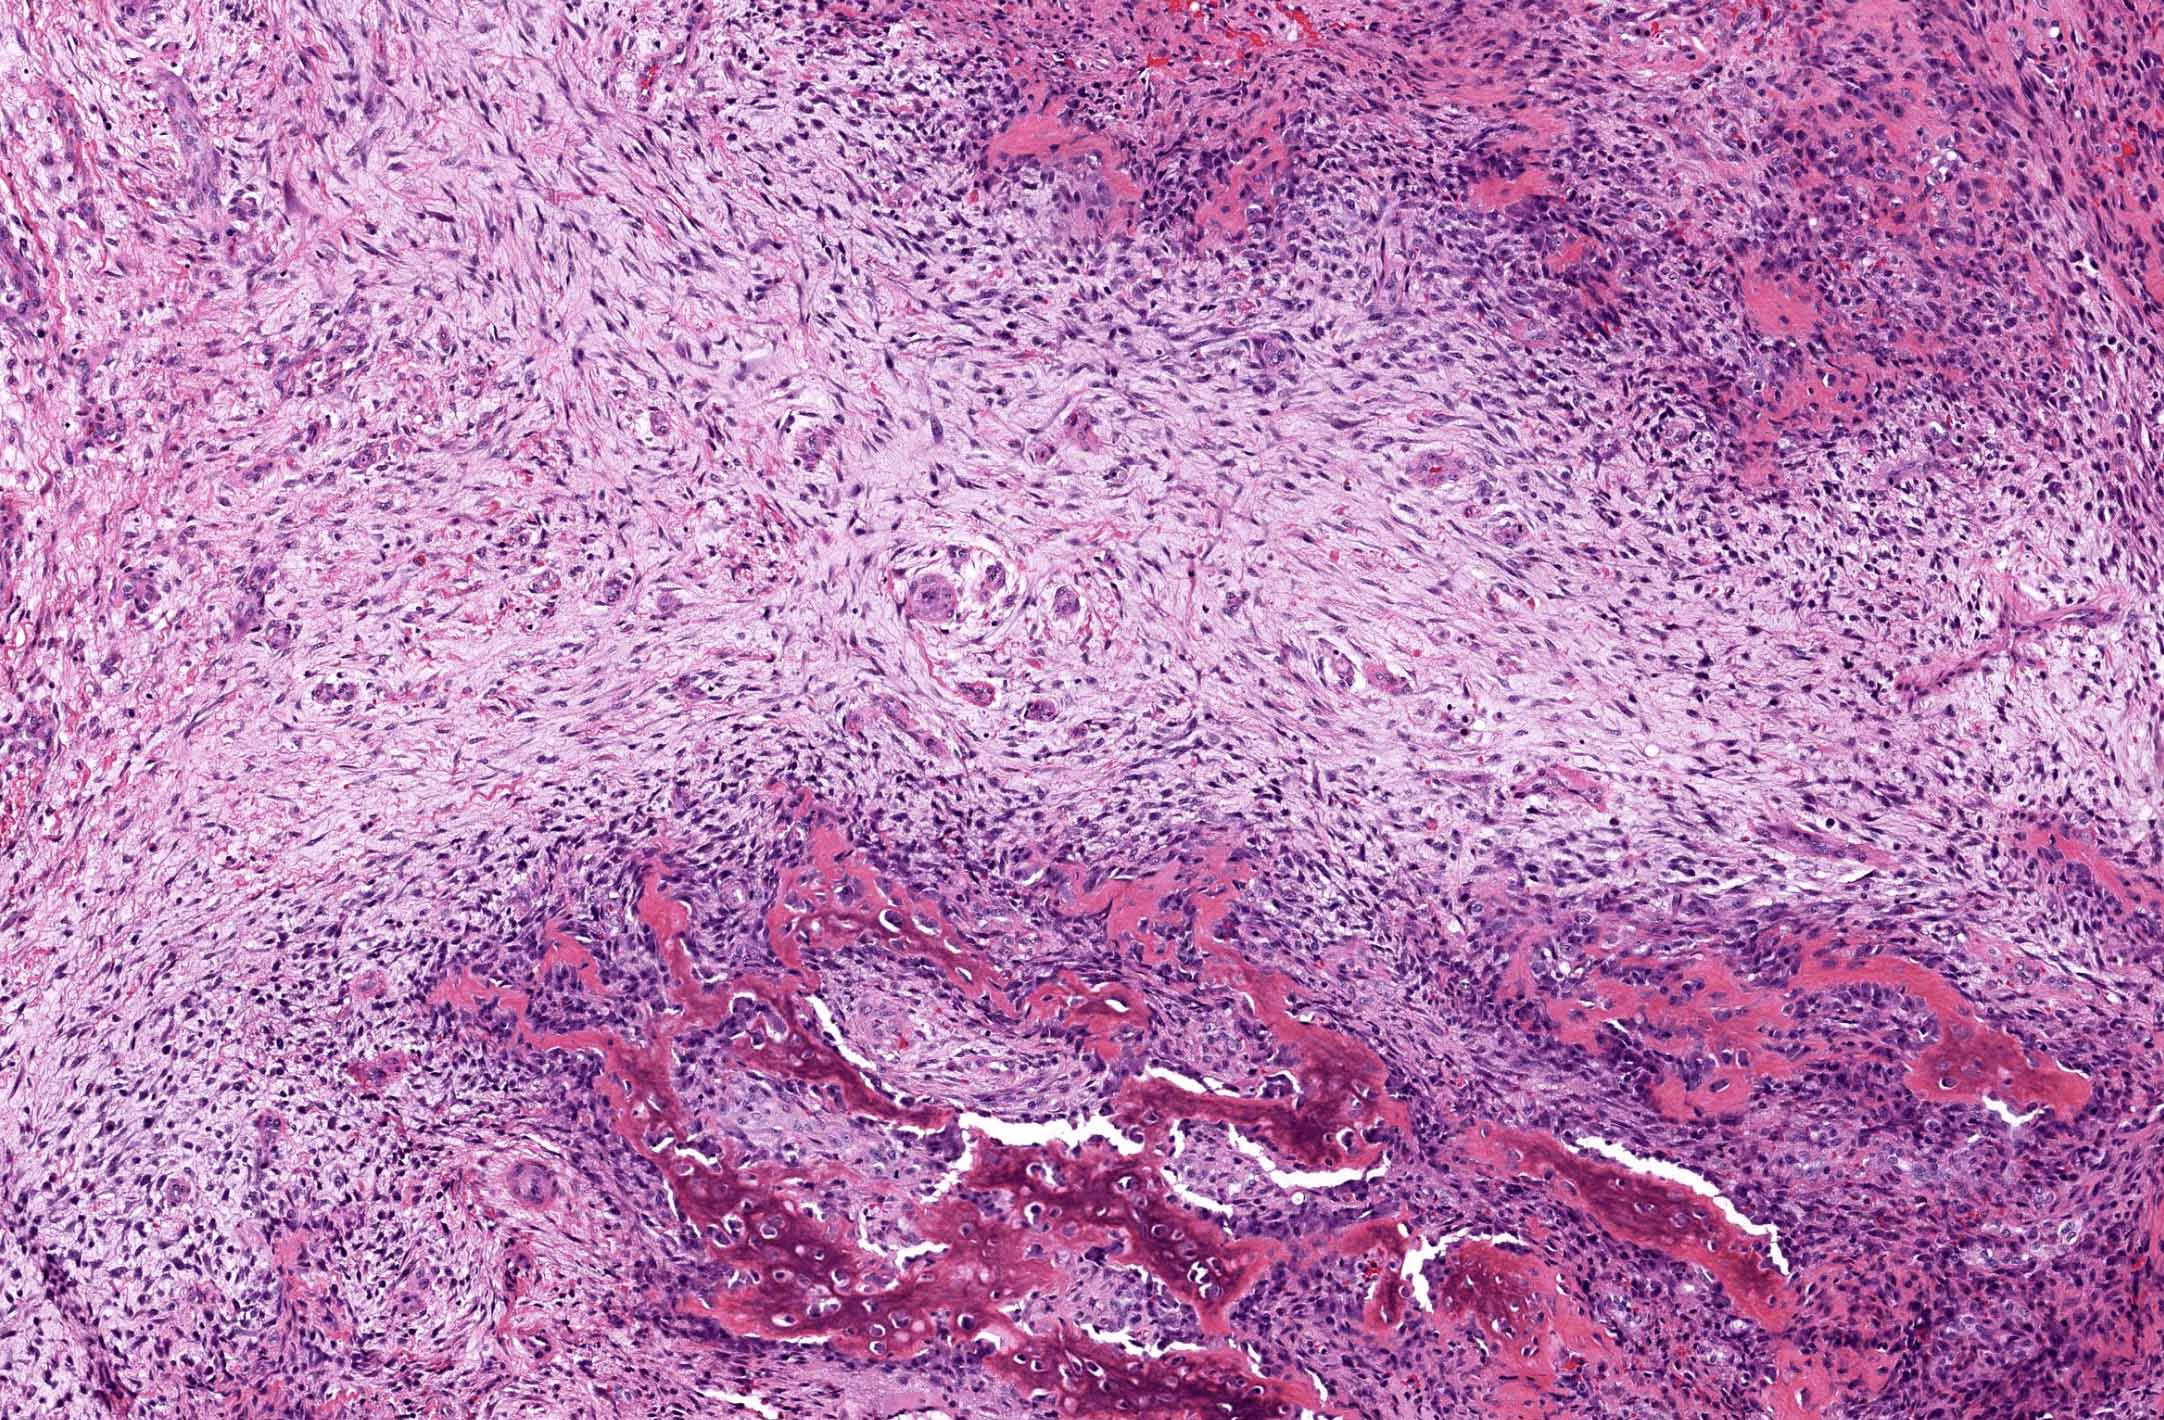

- Histologically, zonal pattern is characteristic with different degrees of cellular differentiation (inner zone, intermediate zone and peripheral zone)

- Inner central zone:

- Composed of fibroblastic / myofibroblastic proliferation, which is richly vascular, rich in inflammatory cells and resembles nodular fasciitis; some multinucleated giant cells may also be seen

- Cells show mild degree of pleomorphism and brisk mitosis

- Areas of hemorrhage, fibrin, endothelial proliferation and entrapped atrophic muscle fibers are noted

- Intermediate zone:

- There is a mixture of fibroblasts and osteoblasts along with erratic osteoid separated by small sized vessels

- Scattered chondrocytes may be appreciated

- Peripheral zone:

- Osteoid undergoes calcification and leads to lamellar bone formation

- Islands of mature or immature cartilage may be present

- Extreme periphery / margin shows mature bone with osteoblastic rimming and little to no pleomorphism

- Lesion is separated from the normal tissue (muscle) by a zone of loose, myxoid fibrous tissue

Microscopic (histologic) images

A 36 year old boxer presented with a painful mass in the right arm for the last 1.5 months. On radiology, an intramuscular mass was seen with peripheral mineralization and central latency. It was biopsied, which showed the morphology in the image above. What is the most likely diagnosis?

B. Myositis ossificans. The given history in this case shows that the patient is physically active and provides short duration history of the lesion. The radiological findings suggest a lesion with maturation at periphery. The microscopic image shows characteristic zonation. These are all features of myositis ossificans.